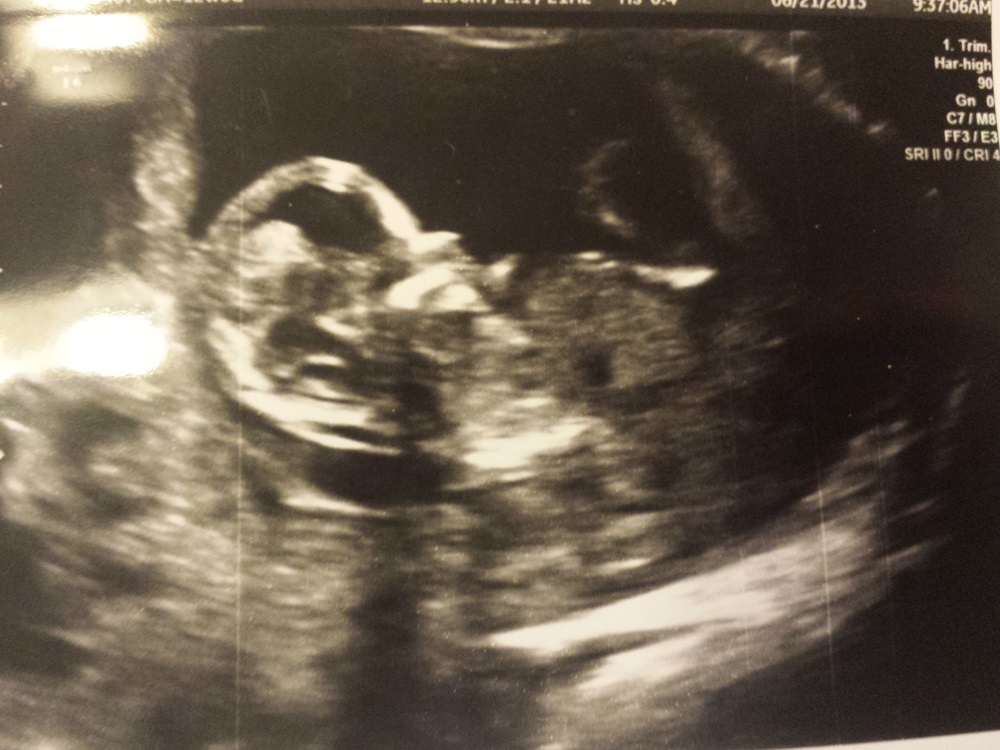

We have our scan in 3 days, on Monday! Take a look at the skull and make your final guess please! Thanks everyone!!!